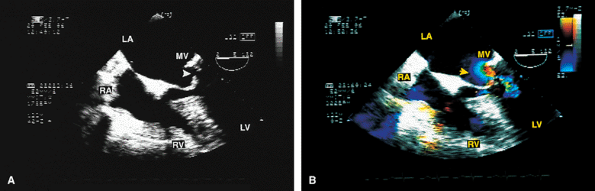

FIGURE 5.5. CarboMedics mitral prosthesis: normal. A–C. Schematics of the CarboMedics mitral prosthesis. In A, the CarboMedics aortic prosthesis is also shown. C. The mechanism of normally occurring MR through the hinge points (courtesy of Sulzer CarboMedics Inc., Austin, TX). D. The prosthesis is seen in the four-chamber view, demonstrating multiple reverberations (1, 2, 3, 4) partially obscuring the left ventricle (LV) and right ventricle (RV) cavities. E. Both leaflets of the prosthesis and the suture ring (arrow) are viewed in the short axis. F. Individual sutures (arrowheads) are seen on the atrial aspect of the prosthetic valve. G. Diastolic flow acceleration (arrowhead) on the atrial aspect of the prosthesis. The LV inflow jet is large. H,I. Two small jets of normal prosthetic valvular regurgitation (arrowheads). R, prosthetic reverberations. AO, aorta; AV, aortic valve; LA, left atrium; LAA, left atrial appendage; MPA, main pulmonary artery; PA, pulmonary artery; RA, right atrium; VS, ventricular septum. |

FIGURE 5.6. A–E. CarboMedics mitral prosthesis: dehiscence of left atrium (LA) wall. A. A small linear echo (vertical arrow) at the site of the paravalvular defect (horizontal arrow) consistent with suture material. B. Color Doppler examination shows a large paravalvular regurgitant jet originating at the site of the paravalvular defect (arrow) shown in A. C. An abnormal 1-cm linear echo (arrow) protrudes into the LA at the midinteratrial septal level. D,E. Multiplane views at 105° and 111° demonstrate a cavitary defect (arrows) involving the LA wall at the midinteratrial septal level, indicative of dehiscence, which explains the presence of the linear echo in the LA seen in C. F–H. CarboMedics mitral prosthesis (MP): LA pseudoaneurysm. F. A large pseudoaneurysm (AN; arrow) that developed following prosthetic replacement (MP, arrowhead) of the mitral valve.G,H. Color Doppler examination shows flow signals (arrowhead in H) moving from the left ventricle (LV) into the aneurysm cavity. AO, aorta; RA, right atrium; RMVP, reverberations from mitral valve prosthesis. (A–E reproduced with permission from Howard J, Agrawal G, Nanda NC. Transesophageal echocardiographic diagnosis of left atrial wall dehiscence. Echocardiography 1997;14:299–302. ) |

FIGURE 5.7. Bjork-Shiley mitral prosthesis: thrombus/pannus. A. A small echo density consistent with thrombus (T) is seen within the ring of the prosthesis (P). B. Its presence is confirmed by the flat diastolic velocity profile (arrows) and a high peak pressure gradient (16 mm Hg) across the prosthesis, consistent with obstruction. C–K. Another patient with a thrombosed Bjork-Shiley mitral prosthesis. Note the spontaneous contrast (SC) echoes in the left atrium (LA) in C, G, and J. I. A thrombus (TH) is well seen on the atrial aspect of the prosthesis (PMV) imaged with a probe in the esophagus, whereas the thrombus on the ventricular aspect is best visualized during transgastric examination (I).Another thrombus (TH) is present in the left atrial appendage (LAA) (G). Color Doppler–directed continuous wave Doppler reveals a very flat diastolic velocity profile with a very high peak velocity of 305 cm/sec, indicative of very severe flow obstruction. K. The arrowhead in J shows prominent flow acceleration on the atrial aspect of the prosthesis. R, prosthetic ring. L. Another patient with a Bjork-Shiley prosthesis. In this patient, the echo density on the ventricular aspect of the prosthesis (P) was found at surgery to be a pannus (PAN) rather than a thrombus. Spontaneous echo contrast (SEC) was present in LA. M. Gross specimen of a thrombosed mitral prosthetic valve. AO, aorta; LV, left ventricle; RV, right ventricle, spontaneous contrast. |